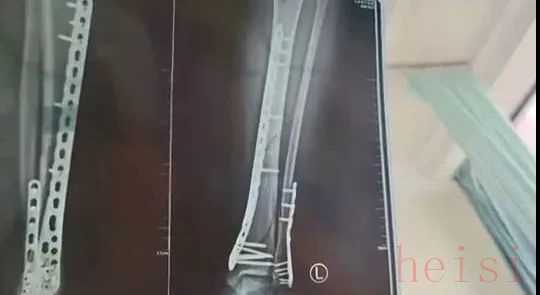

甘肃兰州武女士称

2024年母亲节当天

她穿着7厘米厚的洞洞鞋下楼

不慎崴脚摔倒

致使自己左腿粉碎性骨折